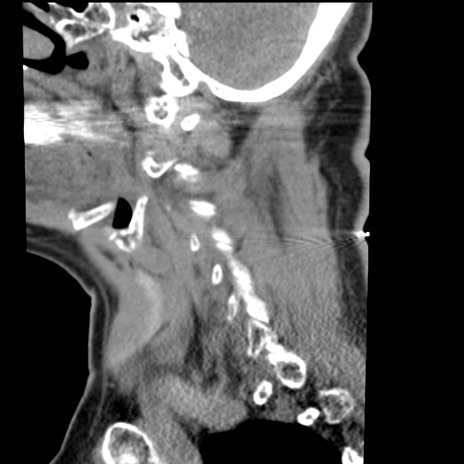

症例50 頚椎CT(矢状断像)

【症例】60歳代女性

【主訴】後頭部〜右後頸部にかけての痛み

【現病歴】本日飲食店でコーヒーを飲んでいたところ、突然後頭部〜右後頸部にかけて痛みが出現し、右上肢の感覚障害を伴ったため救急要請。

【身体所見】脳神経学的に明らかな異常所見を認めず。右上肢に軽度の感覚障害あり。

異常所見と診断は?

横断像

冠状断像